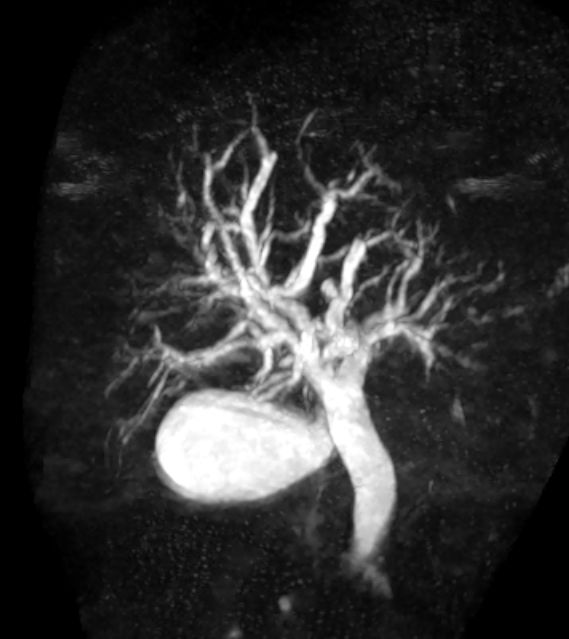

Papille 62-jähriger Mann mit Zeichen der Cholestase. Das CT zeigt erweiterte Gallengänge.

In der MR-ERCP sieht man einen Verschluss der Papilla Vateri.

Nach legen eines Stents keine Cholestase mehr. Aerobili. Histologisch in Nestern angeordnete, relativ monomorphe Tumorzellen mit vergrößerten Zellkernen und aufgelockerter Chromatinstruktur. Eosinroter Zytoplasmasaum. Expression von Synaptophysin und Chromogranin. Ki67 30%.